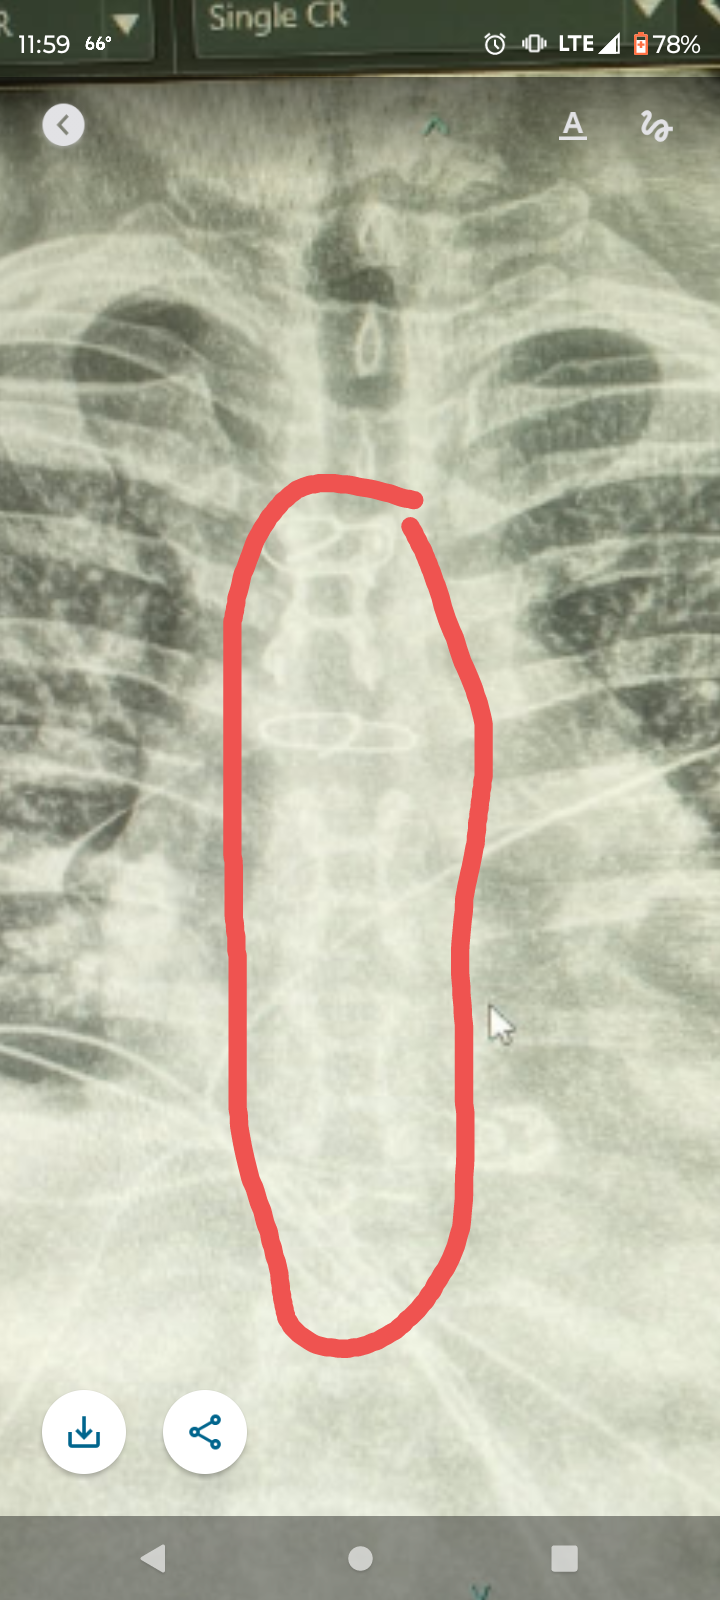

My name is Chris and on April 16th, 2025, I had open heart surgery to perform a pericardiectomy. I'm still out of work and recovering. Unfortunately, we didn't learn I needed surgery until the 11th of April, so I was not prepared to weather 8+ weeks without income. If you are able to help, this will go towards covering monthly bills until I am cleared to return to work. I know times are tougher than ever for everyone, but if you're able to contribute, it would mean the world to me. Thank you.